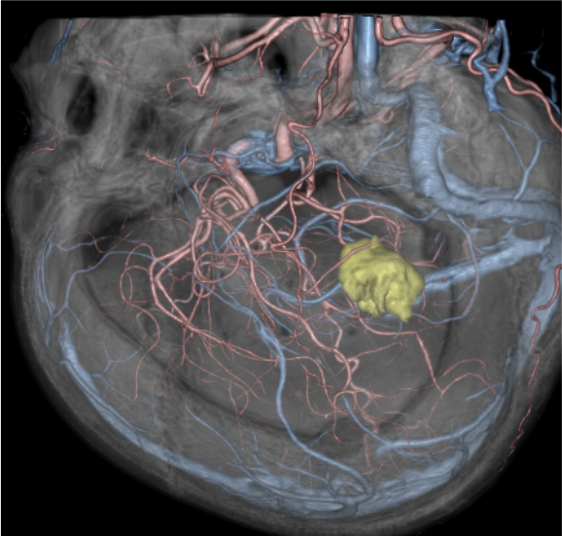

図5.手術支援画像

CTにより骨条件画像、CT angiography、CT venography、造影後期相での増強病変を抽出し、融合して、手術支援画像を作成した。